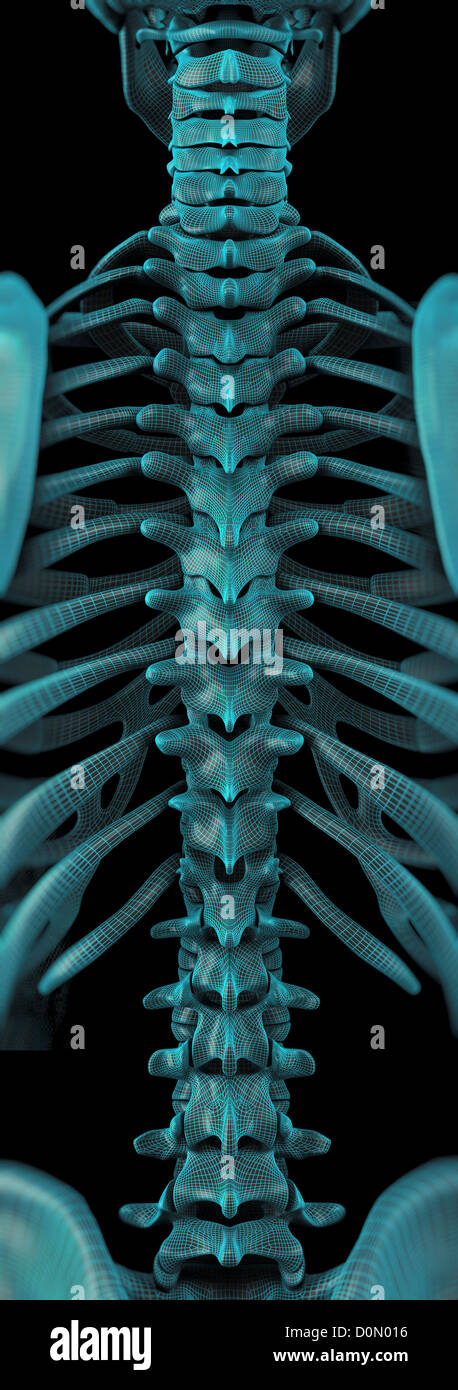

RMJ4C3NM–Questo diagramma di PSM V25 D742 illustra la struttura anatomica delle costole cervicali e il processo trasversale delle vertebre cervicali. È una rappresentazione dettagliata utilizzata nello studio dell'anatomia umana, concentrandosi sulla struttura vertebrale e sullo sviluppo delle costole.

RMPFM8F8–Una guida completa all'anatomia e alla fisiologia, che descrive dettagliatamente la struttura del torace e le variazioni nella formazione delle costole, comprese le costole sovrannumerarie e la presenza di processi trasversali. Il lavoro esplora l'analogia tra processi trasversali e costole, evidenziando le variazioni anatomiche negli esseri umani e negli animali.

RF2KEE32B–Colonna toracica T 1 anatomia ossea per concetto medico 3D Illustrazione con vista anteriore e posteriore

RMMCKTRK–. Â processi trasversali nervatura cartilaginei processo trasversale del 9° vertebra Urostyle

RF2KEE329–Colonna toracica T 11 anatomia ossea per concetto medico 3D Illustrazione con vista anteriore e posteriore

RMMA77DE–. Elementari di anatomia e fisiologia : Per college, accademie e altre scuole . Una vista anteriore dei legamenti delle vertebre e delle costole. 1, la sezione anteriore del legamento vertebrale. 2, il costo anteriore- legamento vertebrale. 3, l'interno legamento trasversale. 4, il Inter-Ar- o sovracapacità per particolari legamento, colleganti la testa della costola al sub intervertebrale- posizione. Una vista dell'articolazione della mandibola, dato dalla segatura attraverso il giunto. 1, la Fossa glenoide. 2, il tubercolo per condilo nel suo avanzamento- zioni. 3, la cartilagine Inter-Articular. 4, il superiore della cavità sinoviali. 5, il file INF

RMW9G8YY–Immagine di archivio da pagina 144 di Cunningham il libro di testo di anatomia (1914). Cunningham il libro di testo di anatomia cunninghamstextb00cunn Anno: 1914 ( le nervature. Ill sfaccettature sulla testa Xeck Xon-articolare parte del tubercolo parte articolare del tubercolo per processi trasversali delle vertebre Fig. 124.-quinta costola destra come visto da dietro. attrezzatura per esterni ed interni dei muscoli intercostali rispettivamente. Sul pavimento della scanalatura può essere visto anche le aperture dei canali per la trasmissione delle navi di nutrienti che sono orientati verso la estremità vertebrale della nervatura. La sezione anteriore o extremi sternale

RF2KEE342–Colonna toracica T 3 anatomia ossea per concetto medico 3D Illustrazione con vista anteriore e posteriore

RMMCKTRP–. .Processi trasversali processo trasversale del 9° vertebra Urostyle Fig. 14.âVertebral.la colonna di Xenopus e rana. La 2a, la terza e la quarta vertebra? Sopportare lunghi processi trasversali curve all'indietro, quelli della terza e quarta fase di ribaltamento con piccole nervature cartilaginei. I processi trasversali del 5°, 6°, 7° e 8° vertebra? Sono sottili e sporgono in avanti e verso l'esterno. Il 9° vertebra ha una lunga ala piana-simili processi attaccati al quale sono i ilia della cintura pelvica. Il urostyle è fusa al 9° vertebra. [In la rana i processi trasversali sono realizzati verso l'esterno e che esse non portano

RMPG3NFM–. Un manuale di zoologia. Zoologia. rsFt. S'i fig. 513. Fig. 514. Fig. 513.-vertebrre caudale di una carpa, sezione (.1) e nearl)' vista laterale (io?). rft, spazio coltivato da notochord; /?, htenial arch; n^ arco neurale; oh^ dorso neurale; %ih^ hsnial colonna vertebrale. Fig. 514.-vertebra toracica, Costole e sterno di un mammifero (da AVieders- heim). Co, testa capitolare della costola; Co, collo di nervatura; Cj>, nervatura ossea; Kn, nervatura cartilaginei; Ps, il processo spinoso; P<, processi trasversali (diapophysis); 5', lo sterno, Th, testa tubercolare di nervatura; WK, centro vertebrale. Il midollo spinale, le parti dell'arco, neurapopliyses, unendo abov

RF2KEE326–Colonna toracica T 4 anatomia ossea per concetto medico 3D Illustrazione con vista anteriore e posteriore

RMPFYCG2–. Cunningham il libro di testo di anatomia. Anatomia. Parte articolare del tubercolo per processi trasversali delle vertebre Fig. 124.-quinta costola destra come visto da dietro. attrezzatura per esterni ed interni dei muscoli intercostali rispettivamente. Sul pavimento della scanalatura può essere visto anche le aperture dei canali per la trasmissione delle navi di nutrienti che sono orientati verso la estremità vertebrale della nervatura. La sezione anteriore o estremità sternale dell'albero, spesso leggermente ingrandita, visualizza un ovale allungata buca in cui la cartilagine costale è affondato. Nervature peculiare.-Il primo, il secondo, decimo e undicesimo di

RF2KEE34K–Colonna toracica T 7 anatomia ossea per concetto medico 3D Illustrazione con vista anteriore e posteriore

RMMA6YGG–. Fisiologia elementare . Processo RANSVERSE ^SUP AR7IC.processo peduncolo Fig. 8.-decima vertebra dorsale, dall'alto. (Disegnata da D. Gunn.) nel caso di tali vertebre per cui le nervature sono allegate (dorsale vertebrse), ciascuno di questi processi trasversali porta una piccola faccetta articolare, per cui un simile aspetto sul corrispondente nervatura è applicato. Sui corpi di questi stessi vertebrse dorsale al di sopra e al di sotto di ogni lato vi è una metà sfaccettatura, che in ogni caso si congiunge con il suo prossimo nella vertebra più vicina per fare tutta una sfaccettatura, per l'articolazione con la testa della costola. In modo tale che ciascuna nervatura ha due punti di interesse

RMPFYCG4–. Cunningham il libro di testo di anatomia. Anatomia. Le nervature. Ill sfaccettature sulla testa Xeck Xon-articolare parte del tubercolo. Parte articolare del tubercolo per processi trasversali delle vertebre Fig. 124.-quinta costola destra come visto da dietro. attrezzatura per esterni ed interni dei muscoli intercostali rispettivamente. Sul pavimento della scanalatura può essere visto anche le aperture dei canali per la trasmissione delle navi di nutrienti che sono orientati verso la estremità vertebrale della nervatura. La sezione anteriore o estremità sternale dell'albero, spesso leggermente ingrandita, visualizza un ovale allungata abisso nel quale le carti costiera

RF2KEE333–Colonna toracica T 6 anatomia ossea per concetto medico 3D Illustrazione con vista anteriore e posteriore